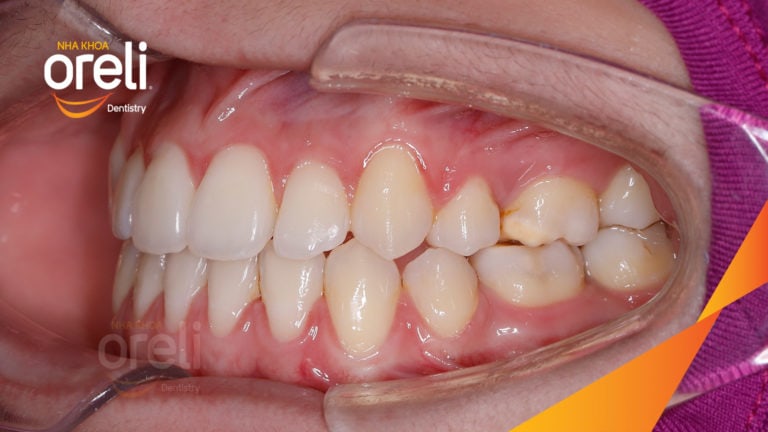

Ca niềng chỉnh chen chúc sai khớp cắn hạng 3 móm nhẹ – Kết quả thực tế ở Oreli Niềng răngChen chúcMóm Xem thêm